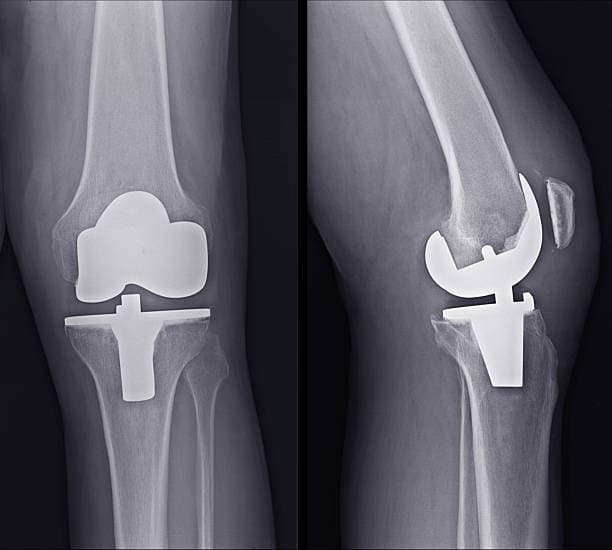

During a total knee replacement surgery, the damaged bone and cartilage are removed from the knee joint and replaced with artificial components. These components typically include a metal femoral component, a metal and plastic tibial component, and a plastic patellar component. The artificial parts are designed to mimic the natural movement of the knee, allowing for improved function and reduced pain. The surgery involves making an incision over the knee, removing the damaged tissue, and securing the new components to the bone using specialized cement or other fixation methods.

The procedure usually takes about one to two hours, and patients typically stay in the hospital for a few days post-surgery. Recovery involves a combination of rest, physical therapy, and gradual return to normal activities. Most patients can expect significant pain relief and improved knee function within a few months, although full recovery can take up to a year. The success rate of total knee replacement is high, with more than 90% of patients experiencing substantial improvement in pain and mobility.

Total knee replacement is considered one of the most successful procedures in modern medicine, with advancements in surgical techniques and materials continually improving outcomes. However, it is not without risks. Potential complications include infection, blood clots, and issues with the artificial joint, such as loosening or wear over time. Despite these risks, the procedure remains a highly effective option for those with debilitating knee conditions, offering a new lease on life for many patients.